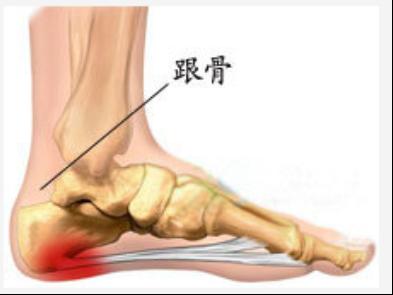

在人体的“骨骼大厦”中,胶原蛋白是钢筋,钙、镁、磷等骨质就是水泥。30岁后,胶原蛋白流失加剧,胶原框架老化变细、变脆甚至断裂,出现缺口;钙、镁、磷等骨质无法正常沉积在骨骼上,从缺口中游离出来;随着肢体的活动和负重,游离的骨质慢慢堆积在活动频繁、承重量大的关键部位(如颈椎、腰椎、膝关节、足跟),骨刺由此产生。